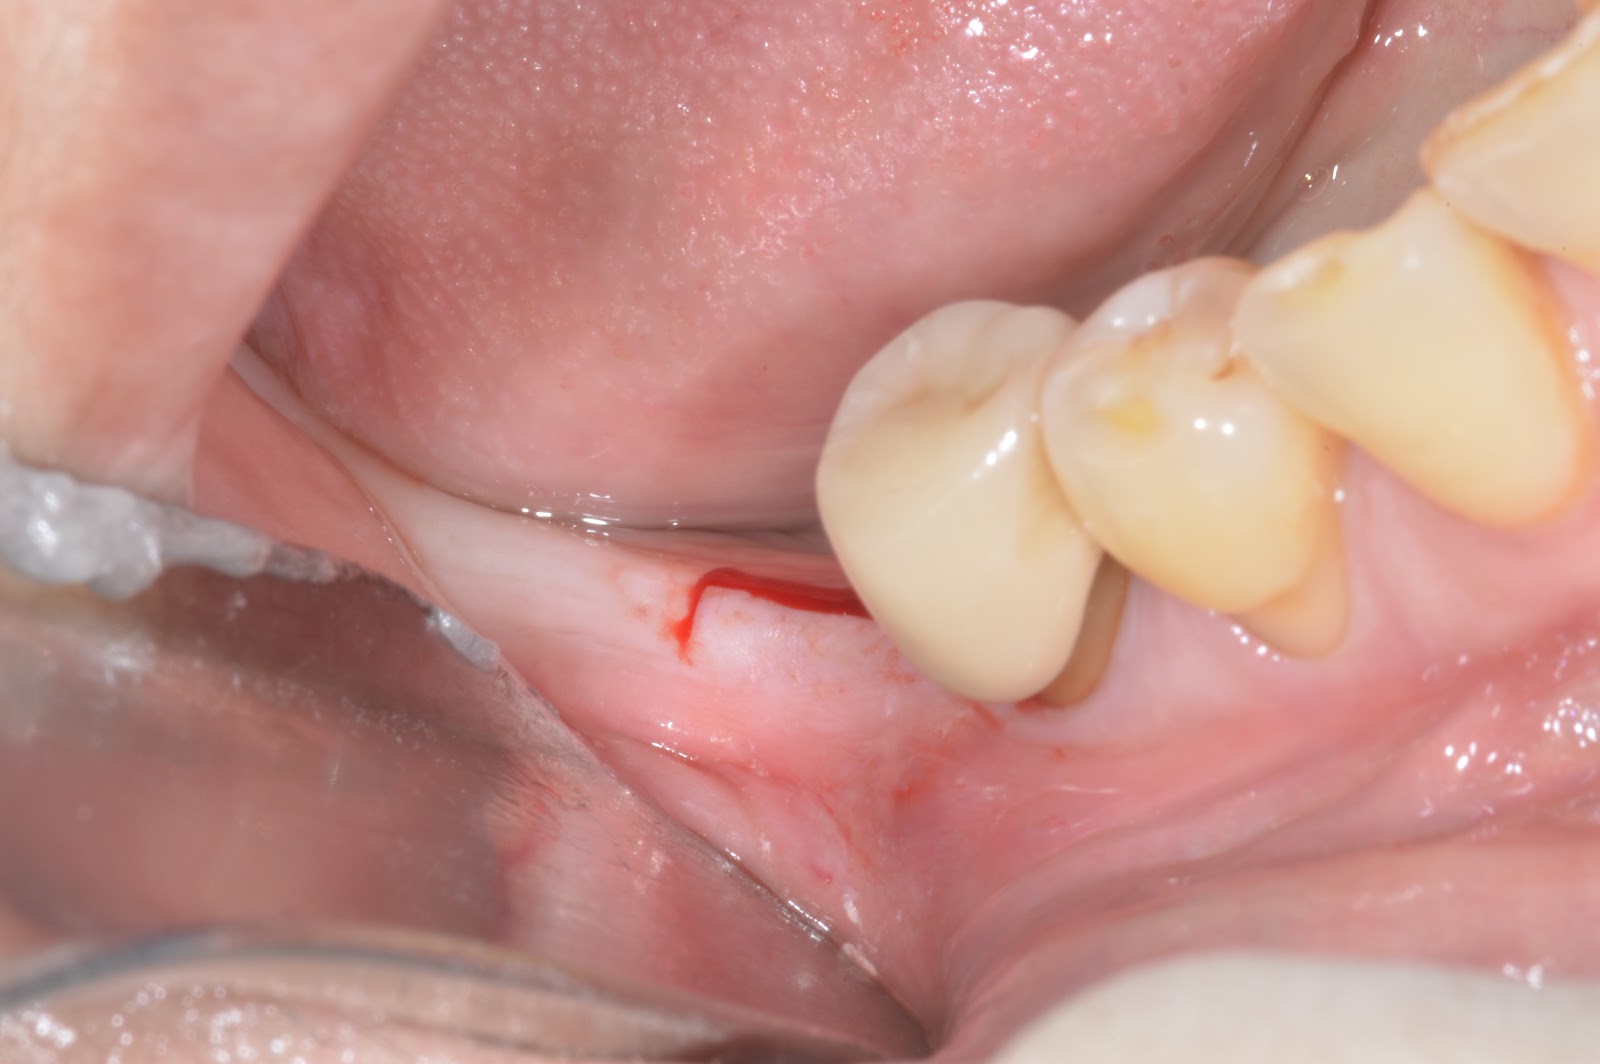

Minimally Invasive Piezoelectric Ridge Splitting

2nd surgery + Terudermis